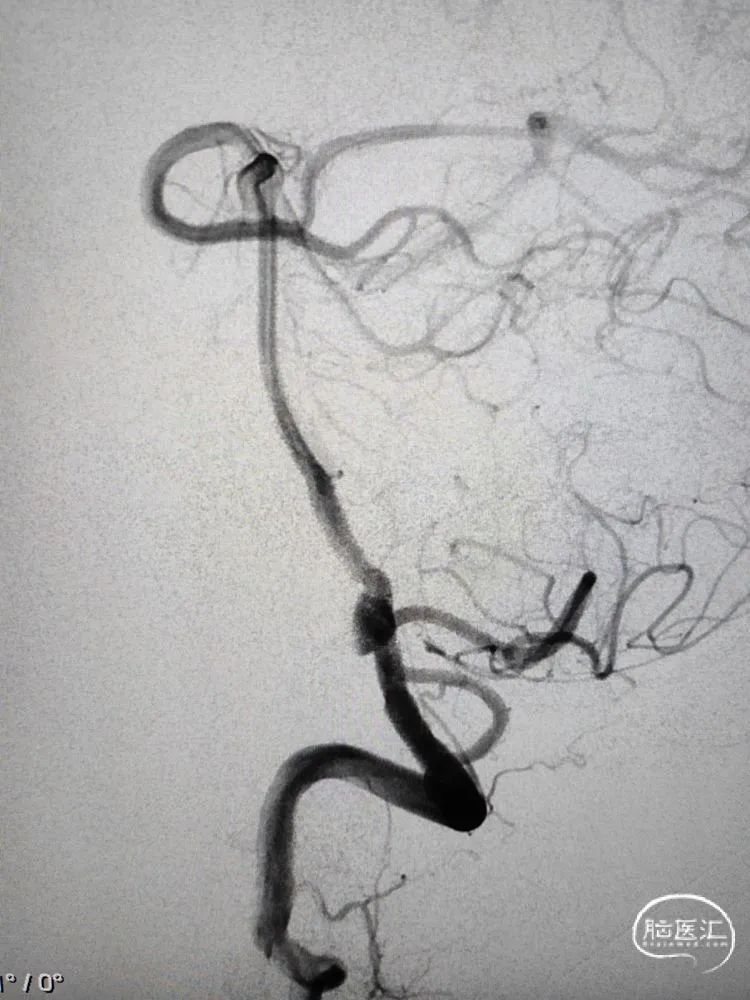

改进版的Tubridge血流导向密网支架到位后,支架在远端预打开再回撤定位,从双椎动脉汇合处下方开始释放,缓慢推出支架进行头端锚定,改进版的Tubridge血流导向密网支架有效改善了头端打开和锚定性能,支架远端刚好落在汇合处下方,造影观察支架充分锚定后,继续缓慢释放支架至瘤颈中段,造影确认后,随后等张释放支架完毕,支架完全覆盖动脉瘤。改进版的Tubridge血流导向密网支架优化了编织丝和编织密度,支架支撑力显著提升,支架打开效果优异,全段充分张开贴壁。

正侧位造影以及三维重建提示动脉瘤瘤囊充盈略减缓,晚期可见造影剂滞留,支架全段完全张开贴壁,载瘤动脉血流通畅良好。